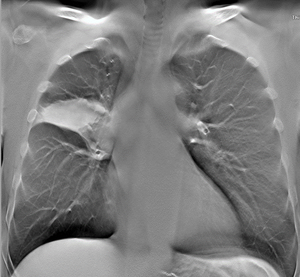

Компьютерная томография органов грудной полости с/без внутривенного болюсного контрастирования